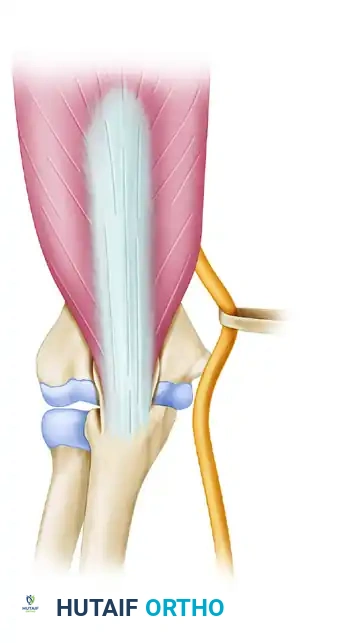

Triceps-reflecting anconeus pedicle approach

Access to distal humerus

Alternative exposures: The modified Kocher lateral approach combined with a medial triceps-reflecting approach provides access similar to an olecranon osteotomy but preserves the extensor mechanism.

Triceps split technique

Split extended to transcutaneous border

The triceps-splitting approach to the distal humerus. While useful for extra-articular fractures or arthroplasty, it limits direct visualization of the anterior articular surface compared to an osteotomy.